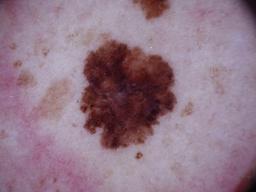

{

"age_approx": 45,

"anatom_site_general": "posterior torso",

"concomitant_biopsy": true,

"diagnosis_1": "Malignant",

"diagnosis_2": "Malignant melanocytic proliferations (Melanoma)",

"diagnosis_3": "Melanoma, NOS",

"diagnosis_confirm_type": "histopathology",

"image_type": "dermoscopic",

"lesion_id": "IL_9993432",

"melanocytic": true,

"sex": "male"

}